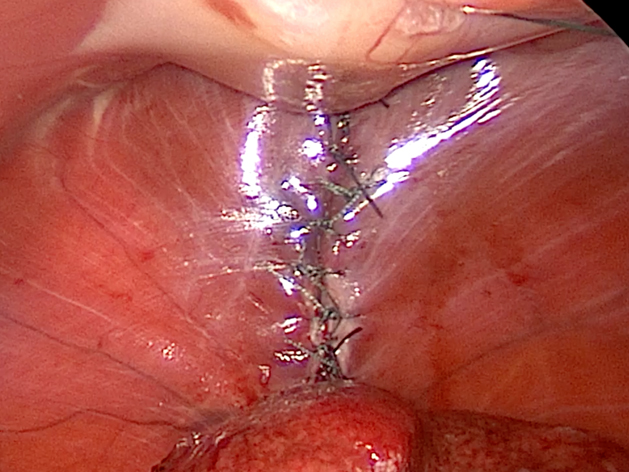

手術の様子

横隔膜を整復した様子